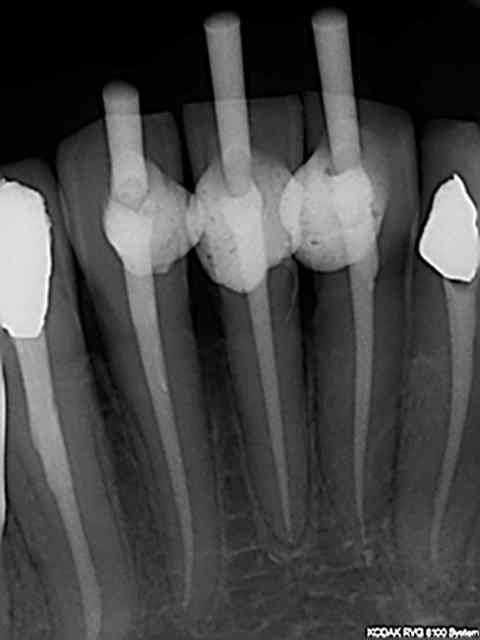

Je viens d'essayer le orange sur 31 41 42, ben il vaut mieux virer le controle de couple sinon tu n'as pas fini. Du coup j'ai dégainé le r25 réciproc et 20 mn plus tard c'était réglé pour les 3.

4 eme degré le R 40, le 50 jamais. A marc , évidemment que tu as raison, mais javais un set d'isi endo qui trainait depuis un certain temps.))))))

En outre, Je "spote" l'apex avec un instrument de rotation continue en 25, monté sur endo master après le r25 (en général mtwo 25).

spoter l'apex en 25 électroniquement avec l'endo master. Les repères visuels sur le r25 (sans localisateur)pouvant etre source d'erreur (minime certes en général ).

Aller à l'apex avec l'instrument du diamètre et de la conicité du cone d'obturation controlé par localisateur (j'utilise le mtwo 25 sur l'endomaster (réglé à -0,5mm de la lt avec fonction reverse à l'apex), il ne force pas du tout et pour cause le r25 est passé avant), d'ou des radios cone en place impeccables à 90% ( 1 fois sur 10 je coupe 1 mm maxi de dépassement). Je rappelle que je mesure la lt initialement avec un S1 protaper sur endomaster.